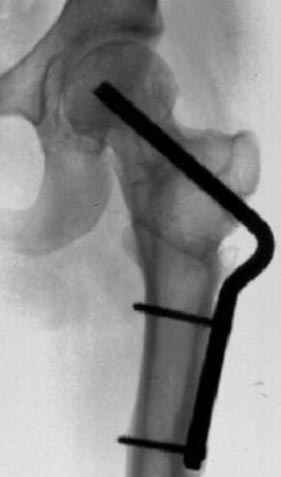

На рисунке N1 предоперационный план лечения ложного сустава шейки бедра- линия ложного сустава, угол и направление введения импланта, клиновидная остеотомия в градусах и миллиметрах, второй снимок после коррекции, расчет, на сколько удлиняется конечность и размеры импланта;

N3 рисунок окончательный снимок, после операции моя рентгенограмма должен выглядеть примерно как эта картина. На N4 снимке клин перед удалением; N5 послеоперации 3 нед.; N6 окончательная рентгенограмма.

Отправитель: Djoldas Kuldjanov 23 Ноябрь 2004, 18:21

пластическая модель; и коррекция бедра аппаратом Илизарова.